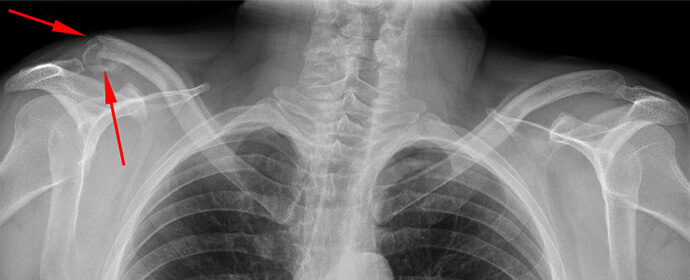

U građevinarstvu radim 25 godina i specijalizirao sam se za postavljanje krova. Prošle godine mi se desila neprijatna situacija – nakon kiše sam se okliznuo na krovu i nezgodno sam pao; srećom nije bilo visoko, samo jedan sprat. Slomio sam ramenu i ključnu kost. Dobro sam i prošao, u mojim godinama je moglo biti puno gore. Morao sam nekoliko mjeseci da provedem u gipsu i bez posla.

Kosti su srasle, ali bol nije nestala. Nisam mogao raditi – i najmanji napor je izazivao paklenu bol, ruka me prosto nije slušala. Doktori su slijegali ramenima. Propisivali su mi snažne tablete protiv bolova radi olakšanja mog stanja. Ispočetka su tablete pomagale, ali onda sam morao povećati dozu. Za neželjene posljedice sam imao bol u stomaku, gastritis i morao sam tražiti druge metode.